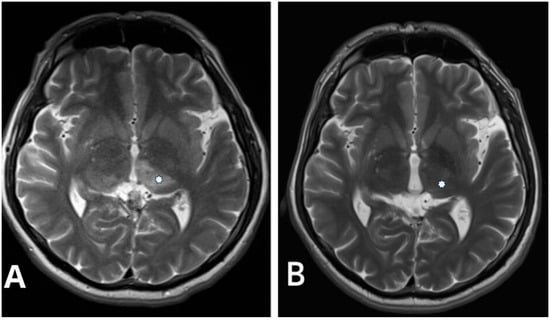

Hemorrhagic manifestations are one of the most critical issues in managing DAVFs due to the increased risk of rupture, particularly in higher-grade lesions. Therefore, classifying DAVF is essential for treatment planning and prognostication. Two commonly used classification systems, the Cognard and Borden classifications, are invaluable tools in this regard. In our study population, the Cognard classification system revealed a predominance of type IV DAVF (Figure 1 and Figure 2), characterized by retrograde leptomeningeal venous drainage with venous ectasia (Table 1). In patients with type IV DAVF, the most common symptoms were headache, nausea and vomiting, and neurologic conditions such as seizure and disorientation due to cerebral venous hypertension, which in our study was neuroradiologically manifested by bilateral thalamic edema in one patient (Figure 2). Classification helps tailor the treatment strategy to the specific characteristics of the lesion.

Figure 2. (A) Pre-procedural T2-weighted axial image in the same patient with Cognard type IV falcotentorial DAVF showing a bilateral thalamic edema (asterisk). (B) Control postprocedural T2-weighted axial image performed 2 years after intervention demonstrates complete resolution of the thalamic edema (asterisk).